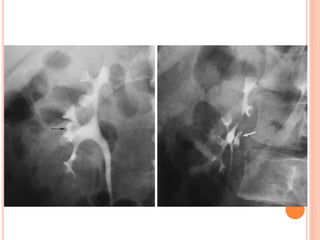

• #26 COMPRESSION

• #27 OBLIQUE